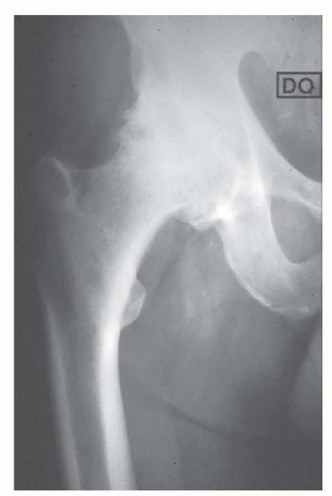

الشكل التوضيحي 1: كشف الحُق. أ. وضعية الاستلقاء للمدخل الجانبي المعدل. ب. كشف الحُق بالكامل. الجدار الإنسي والتشريح الحُقّي الأصلي مرئيان بسهولة. ج. تتم إزالة الشفة الحُقّية. د. يقوم المشرط العظمي بإزالة النتوءات العظمية من الحفرة الكوتيلويدية. هـ. تزيل المكشطة الأنسجة المتبقية لكشف علامة الدمعة.

توضع المباعدات في المواضع الأمامية، العلوية، والسفلية، مما يكشف محيط الحُق بالكامل. تتم إزالة الشفة الحُقّية. تتم إزالة الأنسجة الرخوة في الحفرة الكوتيلويدية، مما يسمح بكشف الجدار الإنسي وعلامة الدمعة.